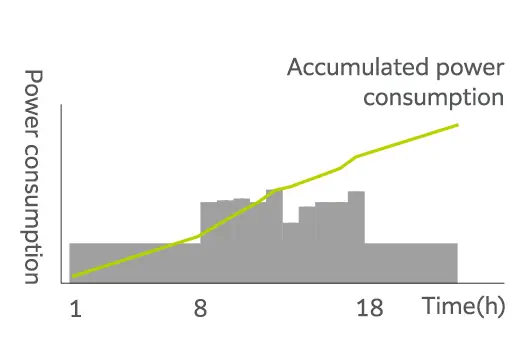

Gereksiz güç tüketimini en aza indirme

Genel olarak, süper iletken MRG sistemi yüksek işletme maliyetiyle bilinir. Bu maliyet esas olarak süper iletkenliği korumak için gerekli olan soğutma sisteminin yüksek güç tüketiminden kaynaklanır. ECHELON Smart Plus, kullanılmadığı dönemlerde soğutma sistemini belirli bir süre durdurabilen bir enerji tasarrufu işlevi olan SmartECO ile donatılmıştır. Bu işlev, helyum kaybına sebep olmadan güç tüketimini etkili bir şekilde azaltır. Dahası, bu süreler boyunca soğutma sisteminden gelen ısı emisyonu azaldıkça, ısı dağıtma ünitesinin güç tüketimi de azalır.

Daha az ısı tahliyesi olan bir MRG ünitesine sahip kompakt bir tarama odası, muayene ve ekipman odalarının iklimlendirme gereksinimlerini de azaltır. Isı tahliyesinin azaltılmasıyla birlikte enerji tasarrufu işlevi çalıştırma maliyetlerini %17*3 oranında azaltabilir